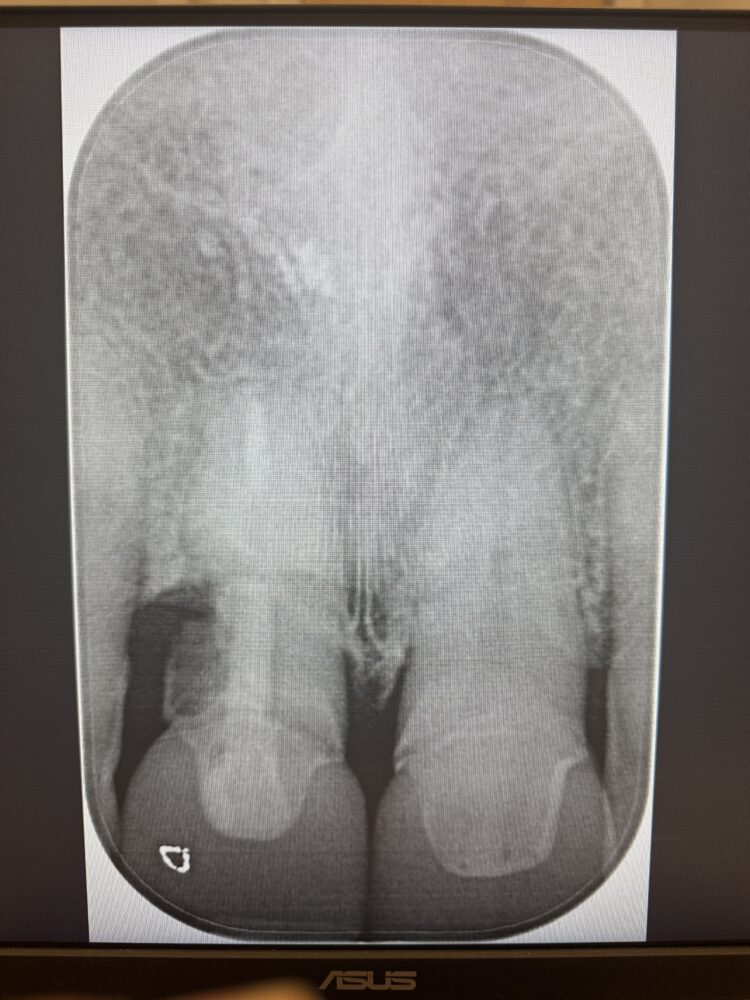

A female patient in her mid-50s was referred due to pain around the gingival margin of the UR1. The tooth had previously been root filled and crowned, and was now unrestorable. External root resorption was confirmed with a periapical radiograph, which showed that the distal bone peak was absent. Located in the aesthetic zone, the missing distal peak meant that the remaining papilla would disappear after the tooth was extracted, and thus needed addressing to avoid the formation of a black triangle.

A post-operative radiograph was taken to confirm that the crestal bone was not compressed and there was no convexity in the area to allow space for the soft tissue graft to expand, proliferate and grow.